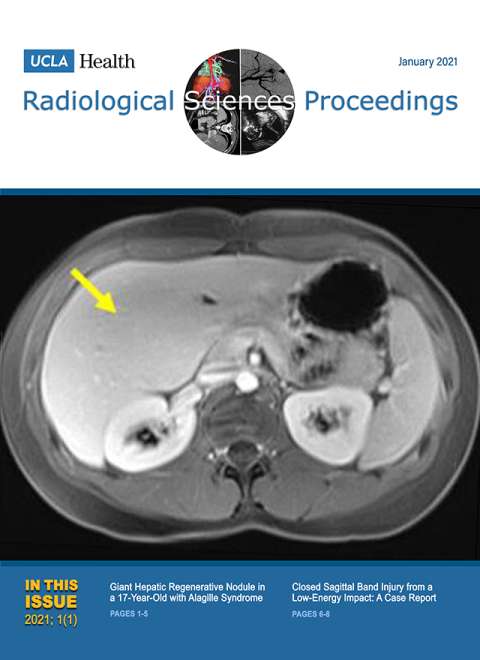

January 2021

Volume 1, Issue 1

- Giant Hepatic Regenerative Nodule in a 17-year-old with Alagille Syndrome

- Closed Sagittal Band Injury: A Case Report.